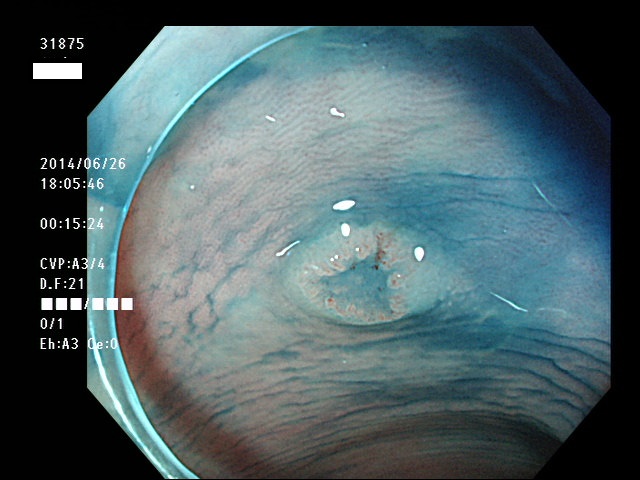

上記100名より抽出した平坦・陥凹型腺腫(=癌化の危険が高いが見落としやすい病変)の内視鏡写真